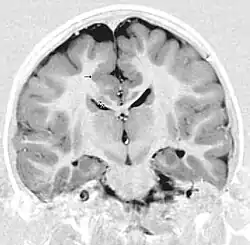

This child presented with seizures. The coronal true inversion recovery sequence shows thickened and disordered cortex in superior frontal and cingulate gyri bilaterally (arrow). There are small convolutions visible at the corticomedullary junction. The appearance is that of cortical dysplasia, with polymicrogyria more likely than pachygyria due to the small convolutions visible. There are also small foci of grey matter signal in the corpus callosum, deep to the dysplastic cortex (double arrows). These probably represent areas of grey matter heterotopia.

There are different tests or methods used to determine GPR56 expression or visuals of the brain to analyze the specific sections that are affected. These tests for example, using animals such as mice, RNAi, Behavioral assay, Electron microscopy, CT scan, or MRI demonstrate different results that concludes an affected BFPP patient.[15] MRI's reveal either irregularity to the cortical surface suggestive of multiple small folds or an irregular, scalloped appearance of the gray matter-white matter junction.

The diagnosis of polymicrogyria is typically made by magnetic resonance imaging (MRI) since computed tomography (CT) and other imaging methods generally do not have high enough resolution or adequate contrast to identify the small folds that define the condition. The cerebral cortex often appears abnormally thick as well because the multiple small gyri are fused, infolded, and superimposed in appearance.[5]

• Radiological findings (MRI) demonstrated symmetric generalized polymicrogyria with decreasing anterior-posterior gradient, most prominent in frontoparietal cortex.[5]

• Numerous gyrus on the cortex

• Small gyri and sulci

• Thin cortex